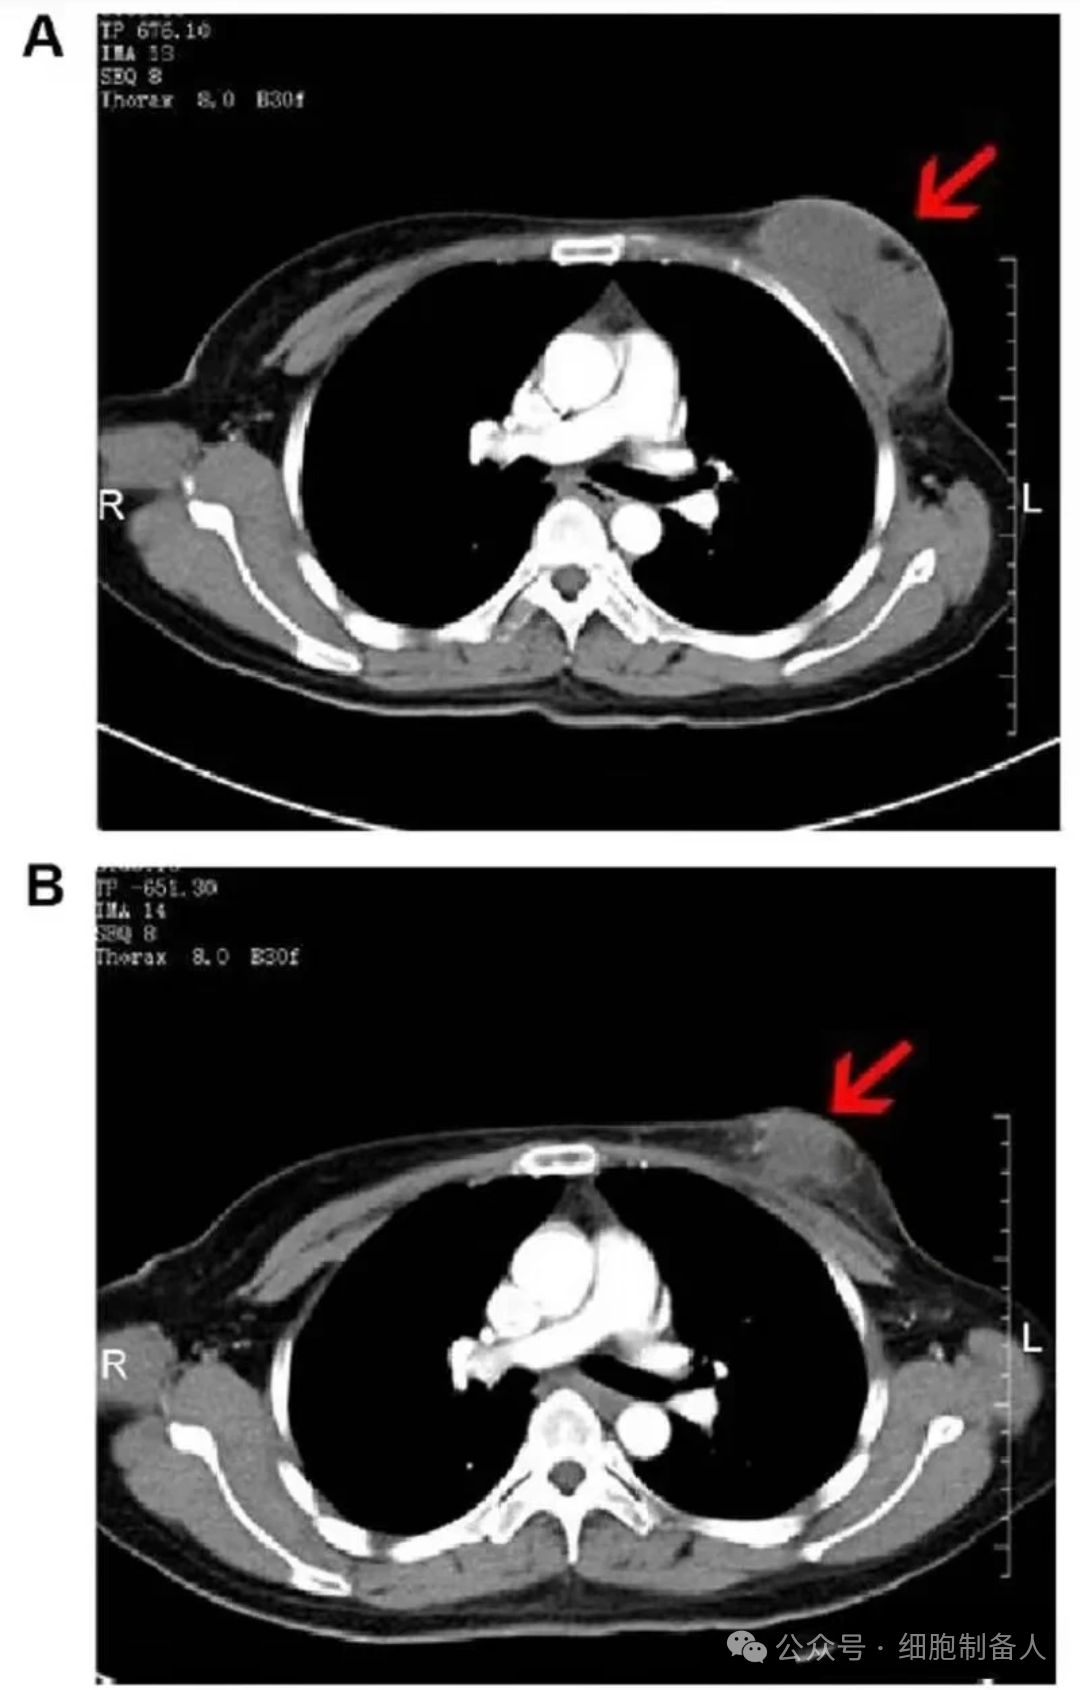

• 肿瘤缩小明显:两组治疗后肿瘤体积均减小,异体组肿瘤最大横径及 CT 值均小于自体组。

• 典型案例:46 岁患者治疗前右乳有 8.0×3.8×5.7cm 肿块及腋窝肿大淋巴结,治疗 2 个月后肿块缩小,肿大淋巴结明显消退。

图片